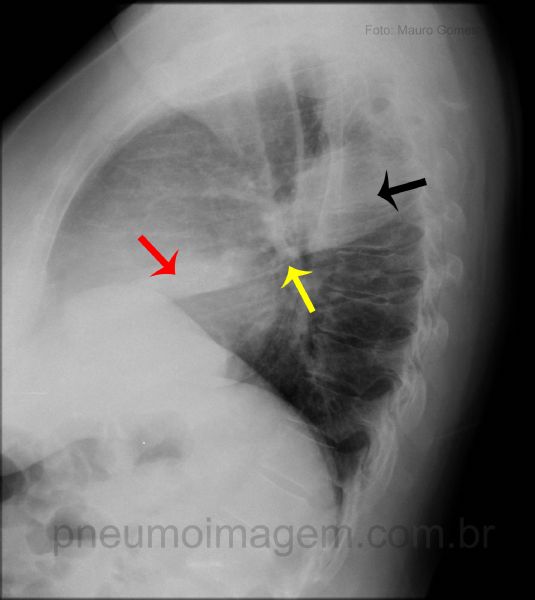

Na incidência em perfil podem-se observar as opacidades no lobo superior direito (seta preta) e no lobo médio, sobre a imagem cardíaca (seta vermelha), delimitadas do lobo inferior direito pela cissura oblíqua (seta amarela).

In the lateral position can be observed opacities in the right upper lobe (black arrow) and middle lobe (red arrow), right lower lobe bounded by oblique fissure (yellow arrow).